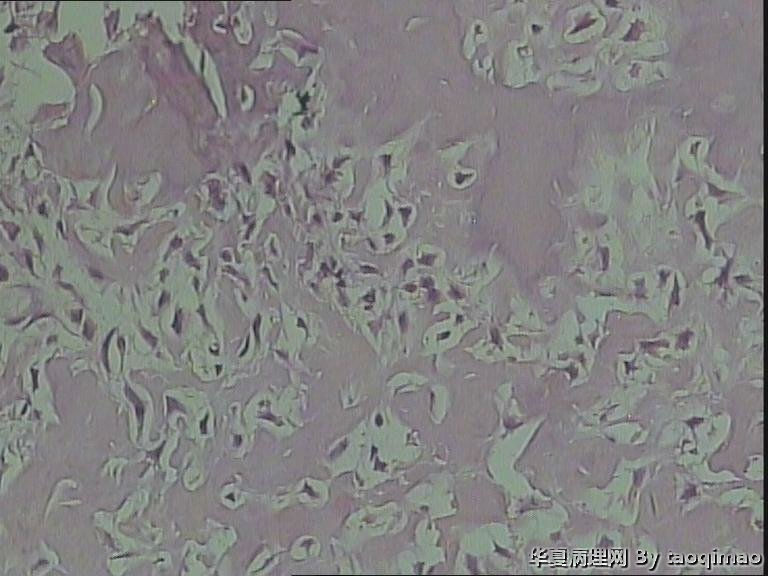

肋骨肿物,求助

这是比较容易取下来的部分,肋骨内部的肿瘤还在制片中

这是一部分容易取下来的肿瘤,其余部分还在脱钙中

患者女,31岁,胸部CT第八肋骨肿瘤,肿物在肋骨内突出骨外膜,大小2.3X1.5.切面灰白质韧

骨母细胞瘤。矿化不均要除外骨母细胞型骨肉瘤,虽然肿块小了点。还是找找核分裂,看看X线的好。

老师不考虑骨样骨瘤么?X线说偏向良性肿瘤

那就是骨样骨瘤。